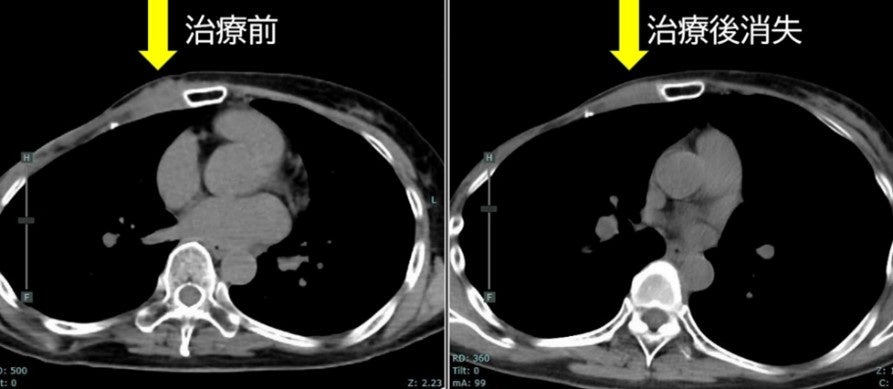

・FDG-PET陽性の浅在性腫瘍に対するBNCT(jRCTs031240204)治療10例目:初発乳がん(未手術)

FDG-PETにおける集積がSUV5からSUV1へ低下。治療1カ月後の時点で触診上腫瘍が確認できなくなり、その後2~4カ月の画像診断においても腫瘍は確認されませんでした。(効果判定はCR)